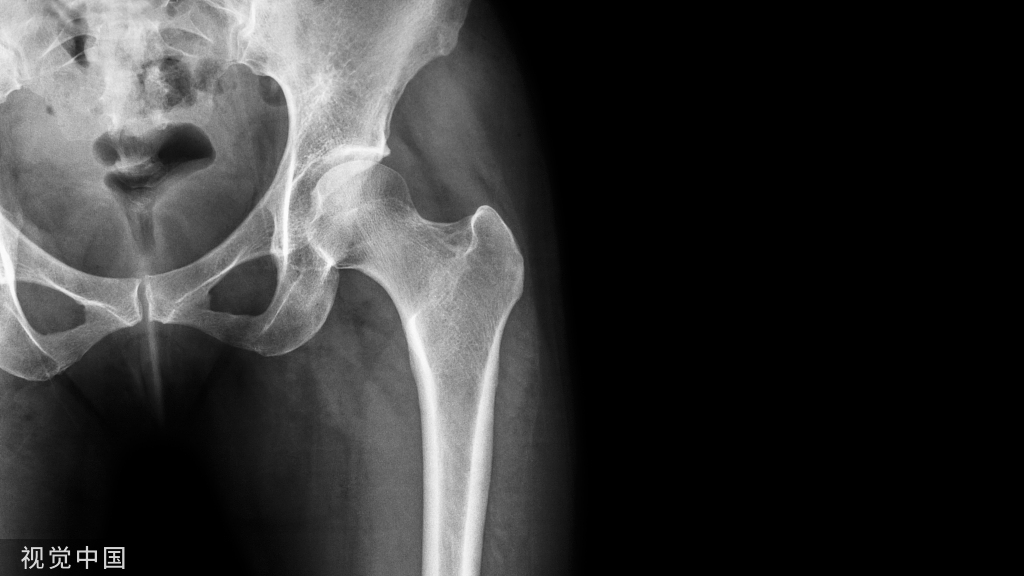

症状性根尖周炎(SAP symptomatic apical periodontitis)从牙髓炎过渡到根尖周炎(图2和3)的发生速度非常快,牙齿表现可能从正常到对冷、热和电刺激的反应越来越强。当牙髓已经完全坏死时,通常会显示对牙髓电活力测试无反应。牙齿可能会有伸长感,用手指或口镜柄施加压力或者振动牙齿会触发非常严重的疼痛。放射学检查可能存在透射区及根周膜间隙增宽,通常硬骨板和牙周韧带没有病理学特征。

图2:46 牙齿SAP。术前X 线片,该牙齿在其他医生处已行龋齿治疗。患者诉牙齿有明显的咬合痛以及强烈的冷热刺激敏感症状。放射学检查,近中根根周膜间隙略增宽。

图3:46 牙齿SAP。根管治疗6个月后。